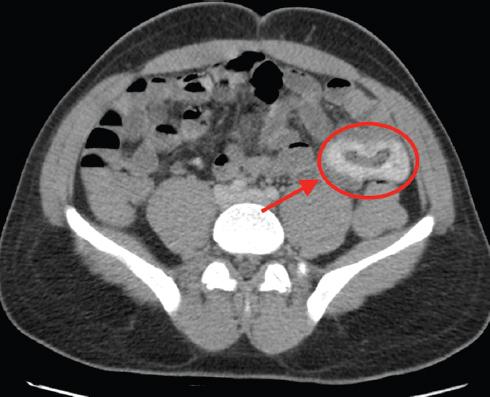

Ante la persistencia de las rectorragias abundantes que comprometían la estabilidad hemodinámica del paciente (120 latidos por minuto, 80/40 mmHg) y que requirieron la transfusión de 11 concentrados de hematíes, se realizó una angiografía por tomografía computarizada (Figs. 1 y 2), que mostró signos de sangrado activo en una lesión tumoral en el yeyuno medio. Se realizó embolización de la arteria dependiente de la arteria yeyunal por parte de radiología intervencionista (Fig. 3), inicialmente con éxito, y el paciente pasó a la unidad de reanimación posquirúrgica, sin precisar fármacos vasoactivos en ningún momento.

Figura 2 En la fase tardía se observa una acumulación de contraste endoluminal en las asas de yeyuno segmentarias.